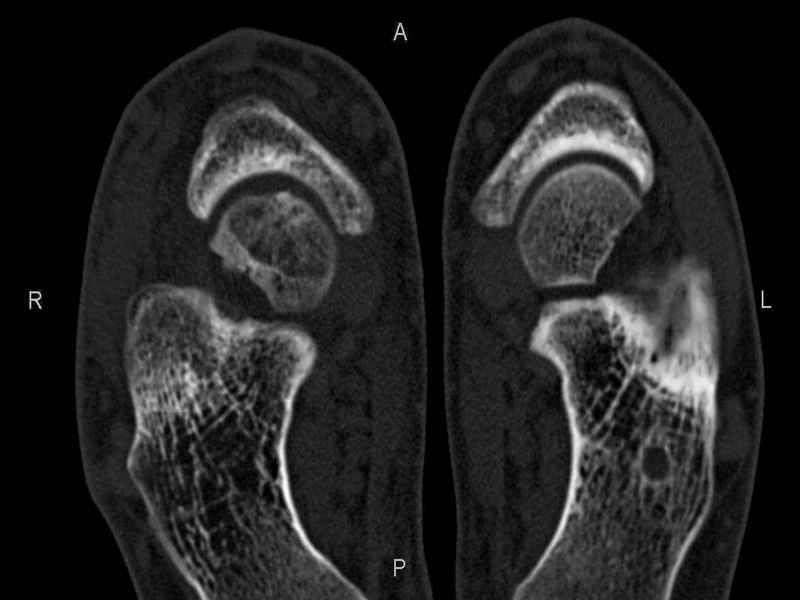

Уважаемые коллеги, обратился за помощью пациент, мужчина, 25 лет. С жалобами на болевой синдром в области голеностопного сустава и среднем отделе стопы. Травму отрицает. Со слов, болевой синдром в течении 1 года. Последние 1-1.5 мес периодически вынужден пользоваться костылями. После ограничения нагрузки боли уменьшаются.Соматически здоров. До появления болей активно занимался рукопашным боем. На СКТ картина рассекающего остеохондрита блока таранной кости, киста шейки таранной кости с признаками импрессии суставной поверхности. А также - разрастания переднего края б\берцовой кости сопровождающиеся клиникой импиджмент синдрома. Предполагаемый план лечения- удаление свободного фрагмента суставного хряща из трансмаллеолярного доступа с рассверливанием поверхности дефекта, кюретаж кисты шейки с заполнением полости биокомпозитом + дебридмент переднего отдела голеностопного сустава. Прошу высказать своё мнение, за и против, предполагаемого плана лечения. А также по возможности ответить на вопросы: 1. Есть ли необходимость в улучшении васкуляризации таранной кости (например подтаранный артродез). 2. Учитывая планируемое применение биокомпозитного цемента целесообразно ли заполнение им дефекта блока таранной кости с моделированием края суставной поверхности.

СТ чётко демонстрирует секвестр, но открыв сустав вероятно, что хрящ тарана окажется интактным и только пальпацией/ ЭОП можно будет

идентифицировать локализацию секвестра. Если вы с этим столкнетесь, то секвестрэктомию я бы предложил сделать не со стороны суставной поверхности тарана, а со стороны угла тарана, субхондрально кюрретаж стенок, разнонаправленную туннелизацию спицей или 1.1мм сверлом и заполнить дефект спонгиозным графтом.